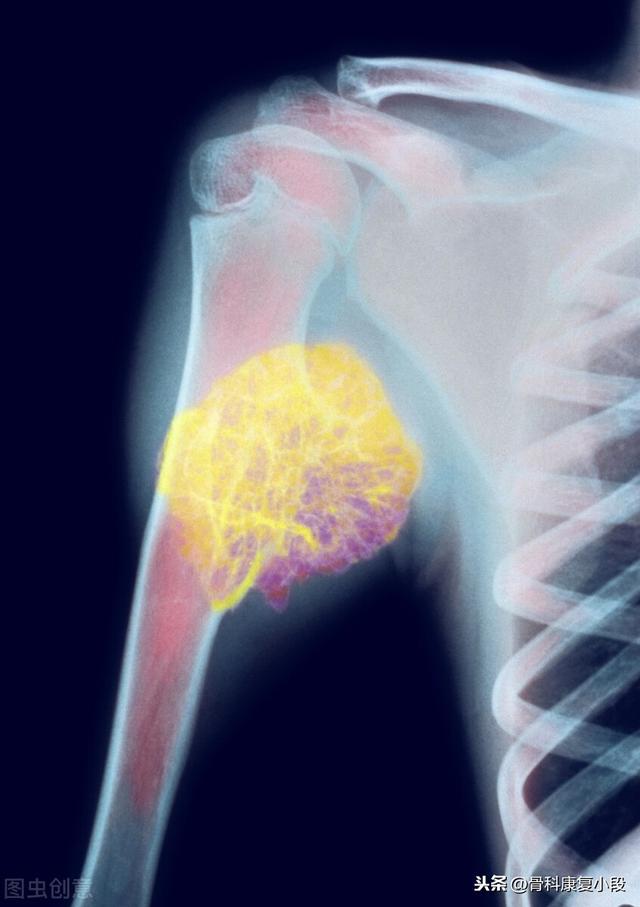

5年間生存している低分化癌の鎖骨転移

この症例は58歳のゲイ男性で、肩を軽く伸ばしただけで痛みが続くようになり、X線検査で低密度病巣が見つかった:

これは骨転移に基づく軽微な外力による病的骨折であった。穿刺が行われ、病理結果は低分化肺腺癌の骨転移であった。

左肺にあるこの不規則な結節が原発巣で、わずか2.6cmしかない。このような骨転移を伴う肺がんは、もはや手術不可能です。肺がんはあまりにもありふれた病気であり、初期症状の中には非典型的なものや無症状のものさえあるからだ。肺がんの約30%では、転移の症状が最初の症状であり、さらなる肺がんが発見される前に転移が最初に発見される。

骨転移で起こる症状にはどのようなものがありますか?最初の症状は痛みです。骨転移を起こした部位は骨が破壊されるために痛みを感じますが、最初ははっきりした症状がなかったり、断続的な痛みだったりしますが、腫瘍が正常な骨をどんどん破壊して徐々に悪くなっていくため、転移部位の痛みも徐々に悪くなっていきます。臨床的には、体のある部分の骨の痛みで、悪性腫瘍の骨転移という症例に出くわすことがあります。以前、ある症例に出会ったのですが、40歳で、肩が痛く、五十肩かと思い、薬用オイルを数日揉んでも改善が見られず、ますます痛みが強くなったので、病院で検査をしたところ、MRIを撮ったところ、肩甲骨が(腫瘍の)かけらに食べられており、骨転移を考え、胸部CTを撮ったところ、右肺に結節があり、生検をして病理検査をしたところ、肺がんの骨転移でした。その内容は以下の通りである。